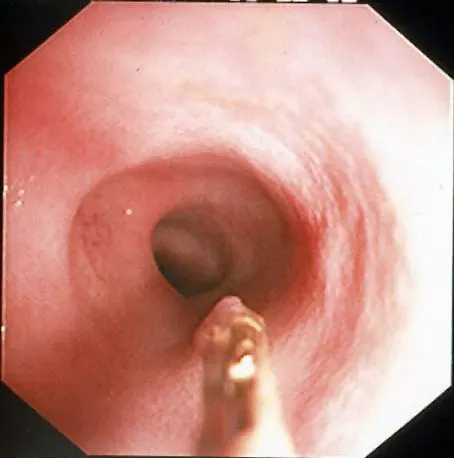

Compared to other alimentary tract organs, the duodenal mucosa has a more granular texture, due to its prominent villous architecture. Duodenal and jejunal mucosa color varies from pale pink to tan in animals having recent biliary secretion. Submucosal lymphoid aggregates appear as oval, slightly depressed mucosal structures present along the descending duodenum (in dogs) and should not be interpreted as mucosal lesions. Other normal mucosal structures include the major duodenal papillae (present in the dog and cat) and minor duodenal papillae (present only in the dog) (Figure 1).

Endoscopic appearance of the normal proximal duodenum in a dog. A lymphoid aggregate (A, arrow) is clearly visible along the lateral mucosal wall. This structure should not be biopsied as such samples confound histologic determination of lymphocytic enteritis. The major duodenal papilla (B, arrow) and a linear mucosal erosion caused by passage of the endoscope through the cranial duodenal flexure are shown in B.

Normal colonic mucosa is pale pink, smooth, and glistening. Submucosal blood vessels are readily observed with adequate insufflation in dogs. Lymphoid aggregates, 2 to 3 mm in diameter and umbilicated, are most common within the rectum and cecum. Visual inspection of the cecum and ileocolic sphincter should be performed in all patients undergoing full colonoscopy. Parasitism, cecal inversion, ileocolic intussusception, inflammatory bowel disease, and neoplasia may cause mucosal lesions in this region.